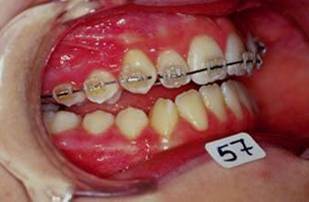

Collage bas fait presque 3 mois apres le haut, avec des elastiques verticaux pendant 3 semaines seulement. Et voici les photos, la suite je vous en passe car il s'agit de simple finition.

Les ponits forts dans cette reeducation sont: maitriser la respiration, reformer le maxillaire, une cooperation extra et une simplicite du system utilise. Merci pour votre attention et a la prochaine... Bonne annee 2007 a tous

En realite les choses etaint deja dans le bon sens des le RDV du collage mandibulaire, si vous regarder les photos 13 et 14, la beance etait deja presque fermee, les elastiques etaient pour eviter que cela ne recidive. Donc le but n'etait pas d'egresser les dents pour fermer la beance mais plutot empecher les deux arcs de s'eloigner.

Comme je l'ai dit, je les ai utilise pendant 3 semaines seulement au moment du collage du bas, apres rien. Les dernieres photos sont presque 3 mois apres le collage du bas et l'arret des elastiques et la beance n'a pas recidive.